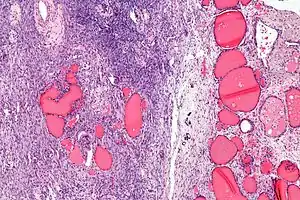

| Micrograph of a struma ovarii. Characteristic thyroid follicles are seen on the right, and ovarian stroma on the left. H&E stain. | |

High magnification Struma ovarii